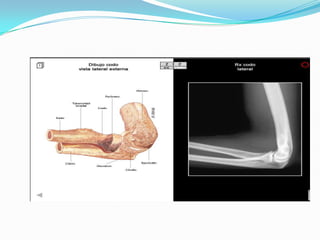

ANATOMIA

Plano Lateral

EVALUACION RADIOLOGICA

 Proyecciones AP y Lateral del codo.

 Deben evaluarse posibles fracturas asociadas a la

articulacion del codo